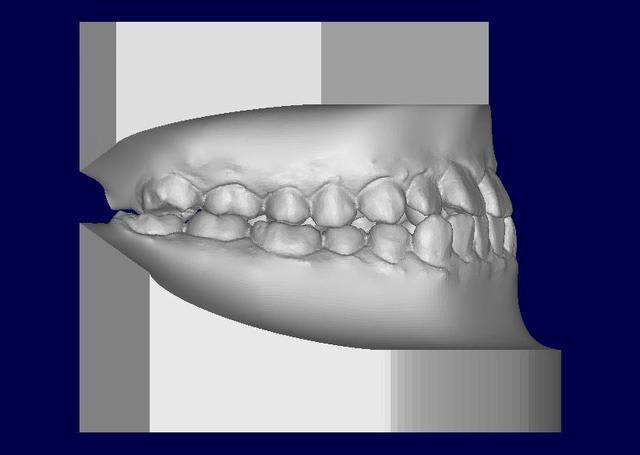

Patient asiatique, 25 ans, consulte car il veut corriger son crossbite bite antérieur localisé aux latérales et son crossbite secteur 2/3. Il aimerait également corriger son apparence générale, son profil notamment.

Classe III squelettique et dentaire.

Pas de shift à la fermeture.

Ci joints photos, ceph, modeles.

il y'a une forte compensation alveolaire maxillaire superieure anterieurement et lateralement,